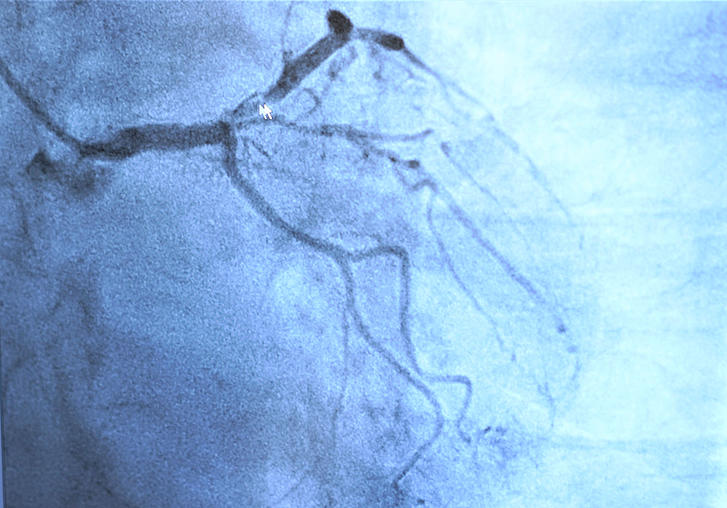

Für die invasive Diagnostik und Therapie der Herzkranzgefäße steht ein besonders strahlungsarmes Herzkatheterlabor zur Verfügung. Die notfallmedizinische Versorgung von Herzinfarkten und instabilem akutem Koronarsyndrom ist rund um die Uhr sichergestellt. In Zusammenarbeit mit der radiologischen Abteilung ist die Kardio-CT und CT-Angiographie etabliert.

• besonders strahlungsarmes Herzkatheterlabor (Philips), Druckdrahtmessung (FFR)

• Behandlung aller Herz/Kreislauferkrankungen, schwerpunktmäßig von Patienten mit koronarer Herzkrankheit, Herzleistungsschwäche und Herzklappenfehlern. Dabei wird das gesamte Spektrum der nicht-invasiven und invasiven kardiologischen Untersuchungen und interventionellen Behandlungen angeboten. Dies umfasst auch die Druckdrahtmessung zur Quantifizierung hämodynamisch relevanter Gefäßverengungen, die Ballondilatation und Stentimplantationen.

• 24-Stunden-Herzkatheterbereitschaft zur schnellstmöglichen Akutbehandlung von Patienten mit Herzinfarkten oder instabilen akuten Koronarsyndromen.